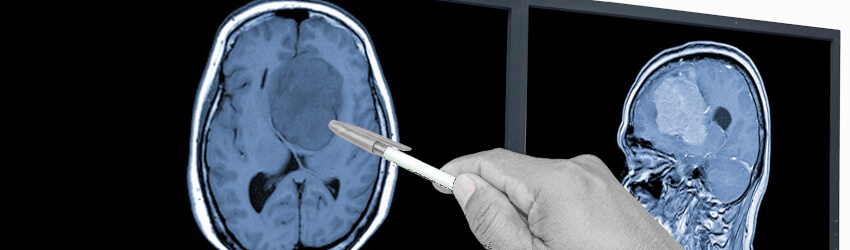

Metabolic process in glioblastoma could unlock new treatments

Targeting a gene-altered metabolic process in glioblastoma (GBM) could unlock new ways of treating the deadly brain cancer.